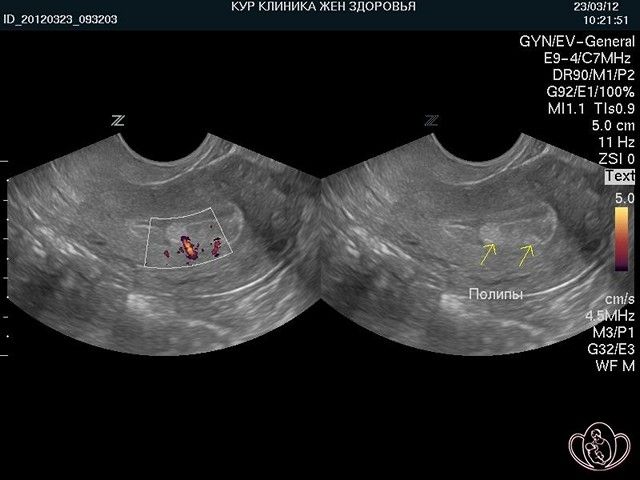

Врачи отмечают, что полипы в матке и эндометрии на УЗИ могут выглядеть как гиперэхогенные образования, которые имеют четкие контуры. Эти образования могут быть одиночными или множественными, и их размеры варьируются от нескольких миллиметров до нескольких сантиметров. При наличии кровотока, что часто определяется с помощью цветного допплеровского картирования, полипы могут демонстрировать усиленное кровоснабжение, что указывает на их активность и потенциальную возможность злокачественного перерождения. Важно, что наличие кровотока не всегда свидетельствует о патологии, однако требует внимательного наблюдения и, при необходимости, дальнейшего обследования. Врачи подчеркивают, что правильная интерпретация УЗИ-данных и комплексный подход к диагностике являются ключевыми для выбора оптимального метода лечения.

Как выглядят полипы на снимке УЗИ?

Ультразвук – это волны, которые при отражении формируют картинку. Жидкости поглощают излучение и являются анэхогенными, выглядят темным пятном. Чем плотнее структура, тем более она эхогенна и светлее. По таким характеристикам можно определить тип ткани, например, кость высвечивается белым и называется гиперэхогенной. Киста с жидким содержимым будет круглым темным пятном с четкими краями.

Железистые образования, как менее плотные смотрятся более темными, чем фиброзные. По тому, как выглядят полипы эндометрия на снимке, невозможно точно определить их разновидность.

Полипы в матке и эндометрии часто становятся предметом обсуждений среди женщин, особенно когда речь идет о результатах УЗИ. Многие отмечают, что на ультразвуковом исследовании полипы могут выглядеть как небольшие, хорошо очерченные образования, которые могут иметь различную эхогенность. Важно, что наличие кровотока в области полипа может указывать на его активность и потенциальную необходимость дальнейшего наблюдения или лечения. Женщины делятся своими переживаниями о том, как результаты УЗИ влияют на их здоровье и планы на будущее. Некоторые отмечают, что своевременное выявление полипов позволяет избежать серьезных осложнений, таких как бесплодие или рак. Обсуждение таких тем в женских кругах помогает повысить осведомленность и снизить уровень тревожности, связанный с диагнозом.

Признаки полипа эндометрия в матке на УЗИ. Полип матки на УЗИ выглядит как новообразование с четким контуром. Другим его признаком может стать расширение полости и утолщение стенки матки. Для диагностики новообразований лучше всего подходят 5-7 дни менструального цикла.